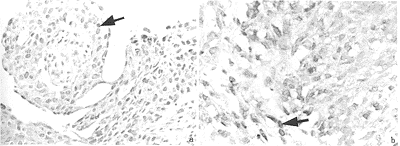

我们首先利用免疫组化的方法检测了14例鼻咽癌活检组织中p16基因表达的改变。作为阳性对照的3例宫颈癌样本都显示明显的核阳性,即p16基因正常表达(图1a)。而在14例鼻咽癌活检组织中只有2例在癌细胞及作为内对照的癌旁上皮细胞内存在明显的核阳性(图1b)。在另外12例鼻咽癌活检组织中,只在癌旁上皮细胞中存在核阳性信号,鼻咽癌细胞中未见核阳性(图1c和1d),这些数据显示这12例(~85%)鼻咽癌活检组织中p16蛋白的表达缺失。

图1 免疫组化检测鼻咽癌中p16蛋白的表达.

a).作为阳性对照的宫颈癌(×200) b).无p16外显子2缺失的19号样本,在鼻咽癌细胞中有明显的核着色(如箭头所示,×400)。

c).有p16外显子2缺失的5号样本,只在癌旁上皮细胞中有明显的核阳性(如箭头所示),但在鼻咽细胞中没有核着色(×400)。

d).无p16外显子2缺失的11号样本,与5号样本一样p16蛋白表达下调(×400)。